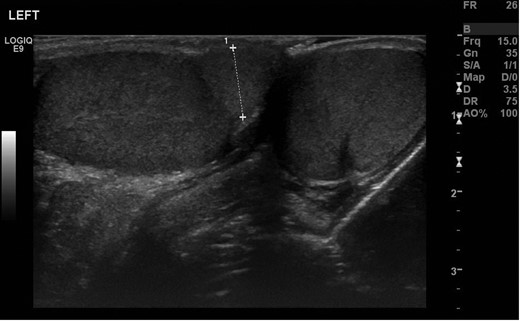

A 12-year-old boy was referred by his GP to the paediatric surgery clinic in a district general hospital with a 6-week history of a lump near the inferior pole of his left testicle. It was non-tender, non-erythematous and had not changed in size or consistency. He was otherwise fit and well, with no family history of urological disorders. On examination, his abdomen was soft and non-tender, with a normal right testis and right spermatic cord. A smooth well-defined lump was palpated on the inferior pole of the left testis. The rest of the testicle had a normal consistency with a normal left cord. Ultrasound demonstrated that both testicles were of a similar size, with normal vascularity and normal epididymi. The palpable lump corresponded to a well-defined 1-cm mass attached to the lower pole of the left testicle (Fig. 1). It had a similar echo pattern to the testicle with normal vascularity (Fig. 2), consistent with the finding of a bilobed testis.

Transverse ultrasonography of the scrotum. A mass is seen attached to the left testicle with the same vascularity as surrounding testicular tissue.